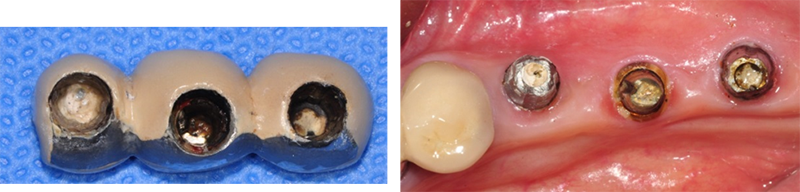

Sub type은 픽스쳐 직경과는 별 개로 어벗은 모두 동일한 사이즈다. 특징이자 장점이다. 픽스쳐가 부러지지 않아서 다행이다. 그러나 어벗의 밑동이 부러진 것도 매우 큰 합병증이다. 부러진 밑동을 깨끗하게 빼내는 것도 상당히 힘든 일이다.

37번 4.3 직경의 원플란트

제거하다가 흠집이 날 것 같아서 포기하고

다음에 약속 잡았는데 환자도 저도 미루다가 이 지경됨.

파노라마 상

결국 픽스쳐 제거

아마도 교합에 문제가 있었던 듯

37번 abutment 파절, 뒤쪽에 8번이 보이고, fixture 직경이 5.0, 조금 흠집이 나도 된다는 생각으로 제거수술을

했다.

3번에

나눠서 겨우 제거한 경우